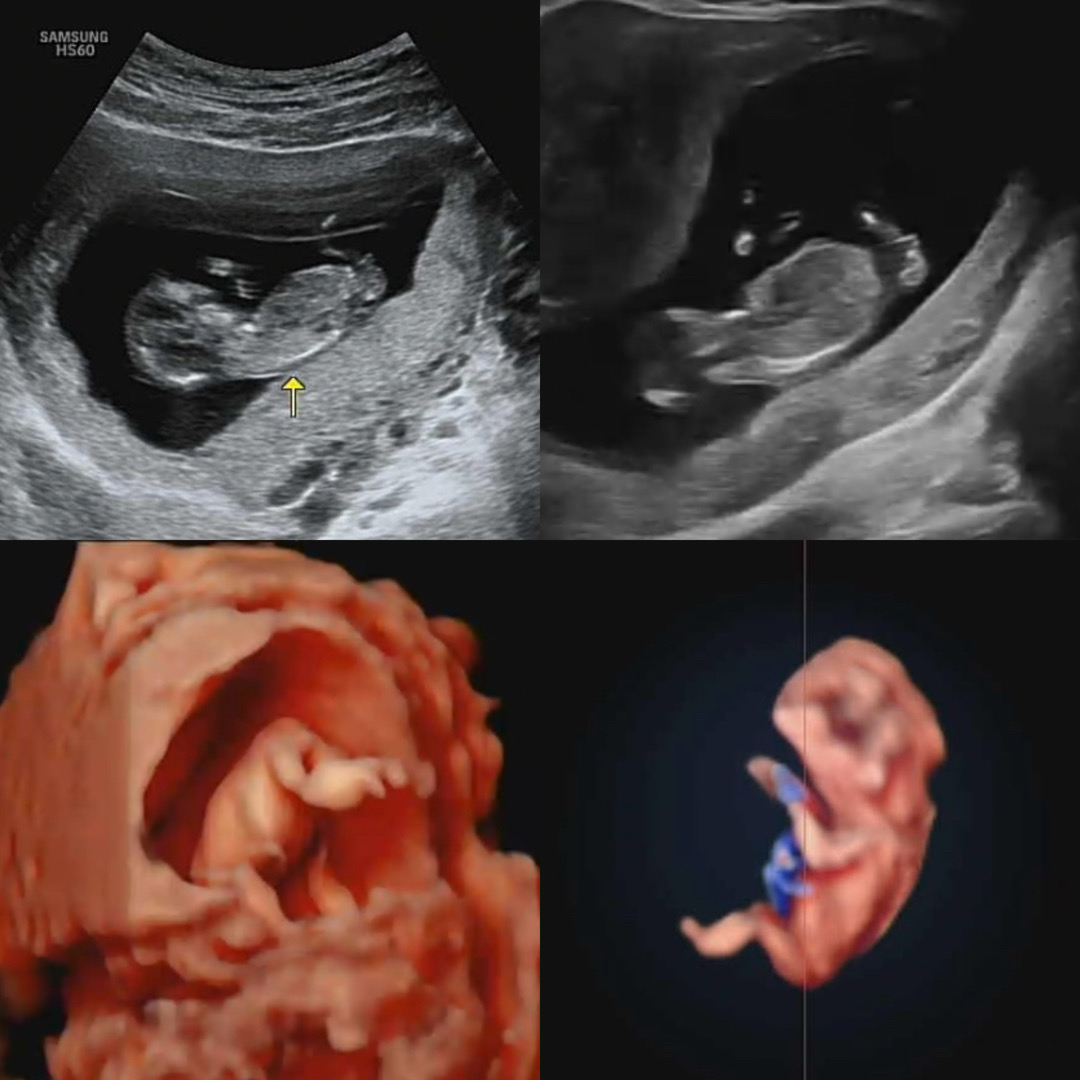

애기 성별이 궁금해요 고수님들 부탁드려요